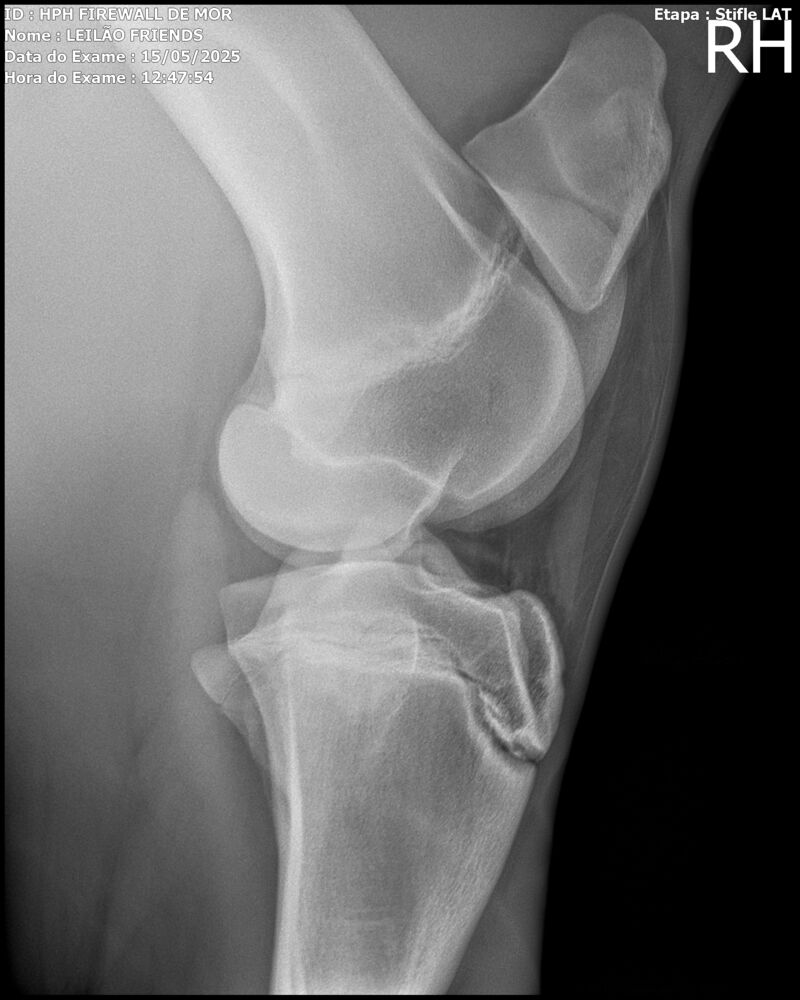

Sexo: MACHO

Nascimento: 13/04/2023

Pelagem: TORDILHA

Altura aproximada: 1,61m

Previsão de altura: 1,66m

Vendedor: HARAS HPH / TRV

Localidade: SÃO PAULO/SP

Garanhão tordilho, apesar de jovem, mostra muito poder e uma plástica de salto incrível. Firewall é sempre muito positivo, busca o salto e os supera com muita agilidade e leveza.